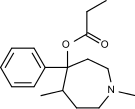

The first fully synthetic opioid was meperidine (later demerol), found serendipitously by German chemist Otto Eisleb (or Eislib) at IG Farben in 1932.[228] Meperidine was the first opiate to have a structure unrelated to morphine, but with opiate-like properties.[199] Its analgesic effects were discovered by Otto Schaumann in 1939.[228] Gustav Ehrhart and Max Bockmühl, also at IG Farben, built on the work of Eisleb and Schaumann. They developed "Hoechst 10820" (later methadone) around 1937.[230] In 1959 the Belgian physician Paul Janssen developed fentanyl, a synthetic drug with 30 to 50 times the potency of heroin.[211][231] Nearly 150 synthetic opioids are now known.[228]

Phenylpiperidines

- Pethidine (meperidine)